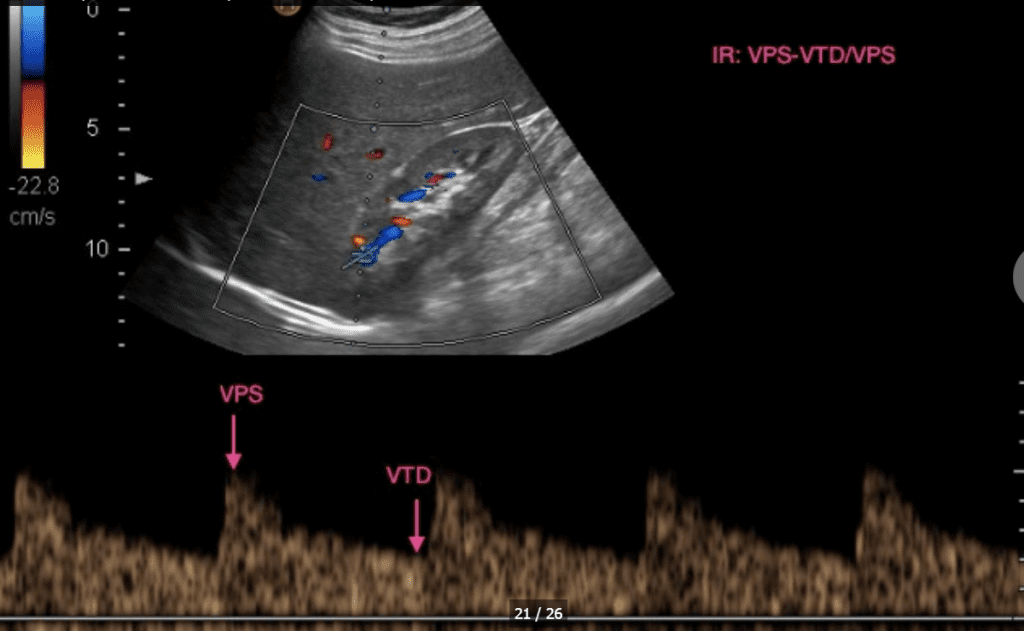

El doppler espectral consiste en una curva de velocidad versus tiempo, que representa la variación de la velocidad de flujo de los glóbulos rojos a lo largo del ciclo cardiaco. El tiempo es representado en el eje horizontal y la velocidad en el vertical.

Índice de Resistencia (RI): En neonatos, el RI generalmente se encuentra en un rango de 0.60 a 0.80, aunque puede variar dependiendo de la ubicación de la medición dentro del árbol vascular renal. Por ejemplo, el RI en las arterias centrales tiende a ser más alto que en las arterias intraparenquimatosas.[1-2]

Índice de Pulsatilidad (PI): El PI mide la variabilidad del flujo sanguíneo durante el ciclo cardíaco. En neonatos, el PI también muestra variaciones dependiendo de la ubicación de la medición, siendo más alto en las arterias centrales en comparación con las intraparenquimatosas.[1]